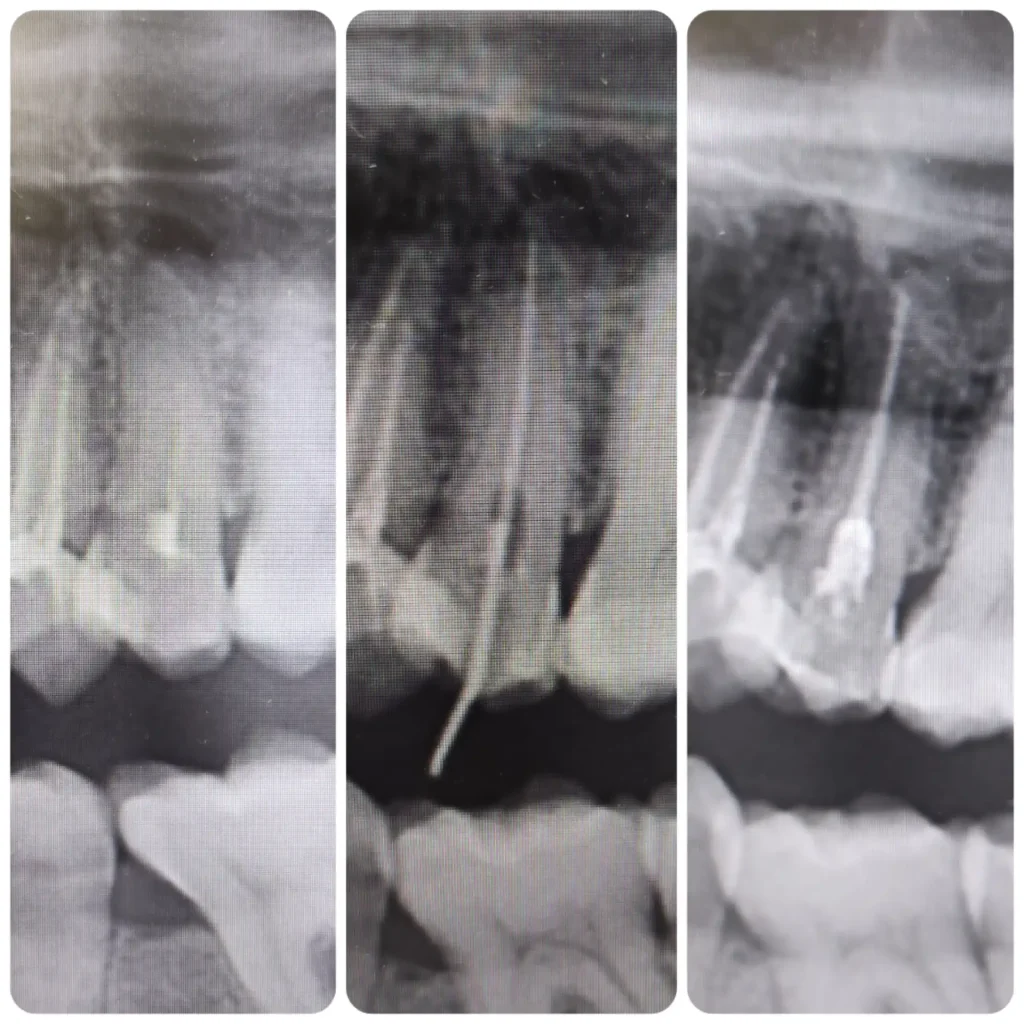

Fő érdeklődési területeim közé tartoznak az esztétikai beavatkozások, tömések, könnyebb gyökérkezelések, hagyományos fogpótlások készítése, kivitelezése. Fontosnak tartom a fogak megfelelő rehabilitációját és szájban tartását. Tudásomat hazai és külföldi szakmai továbbképzésekkel folyamatosan fejlesztem.

Esztétikai és fogmegtartó kezelések mellett nagy érdeklődéssel fordulok a fogszabályozás szakirány felé. Jelenleg fogszabályozási rezidensként sajátíthatom és mélyíthetem el tudásomat a harmonikus és funkcionálisan megfelelő harapás és esztétikai megjelenés kialakításában.